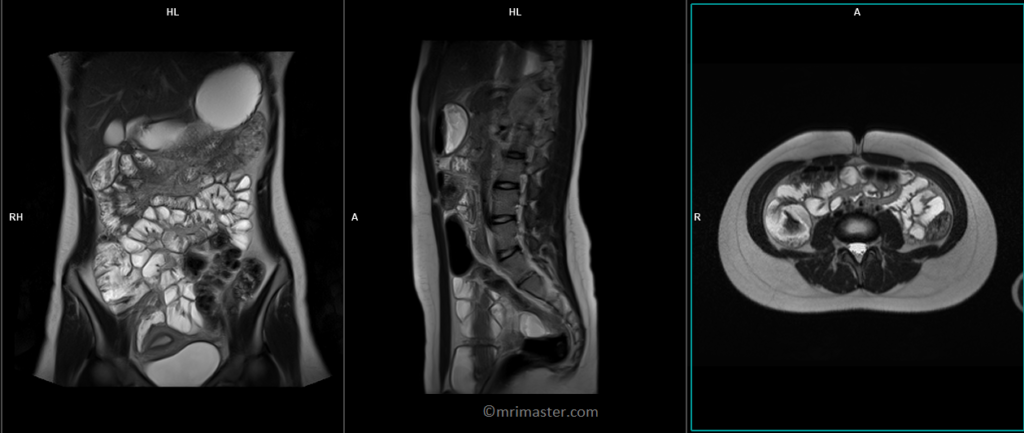

Enterography MRI Localizer

To localize and plan the sequences, it is necessary to obtain an initial three-plane HASTE localizer. These fast single-shot localizers have an acquisition time of under 25 seconds, making them ideal for accurate localization of abdominal structures.